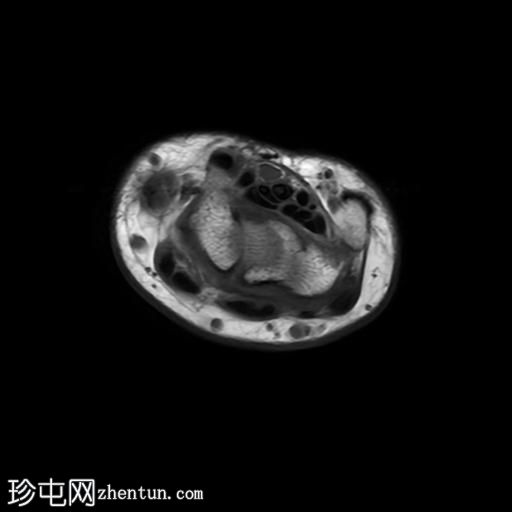

轴向

T1

MRI显示腕部第一背侧肌腱(拇长展肌和拇短伸肌)增厚,并伴有异常增厚的实质内液体信号。腱鞘内液体增多。

尺侧腕伸肌腱可见异常线性实质内液体信号增多,与板状间质撕裂相关。

MRI表现和临床表现提示De Quervain腱鞘炎。